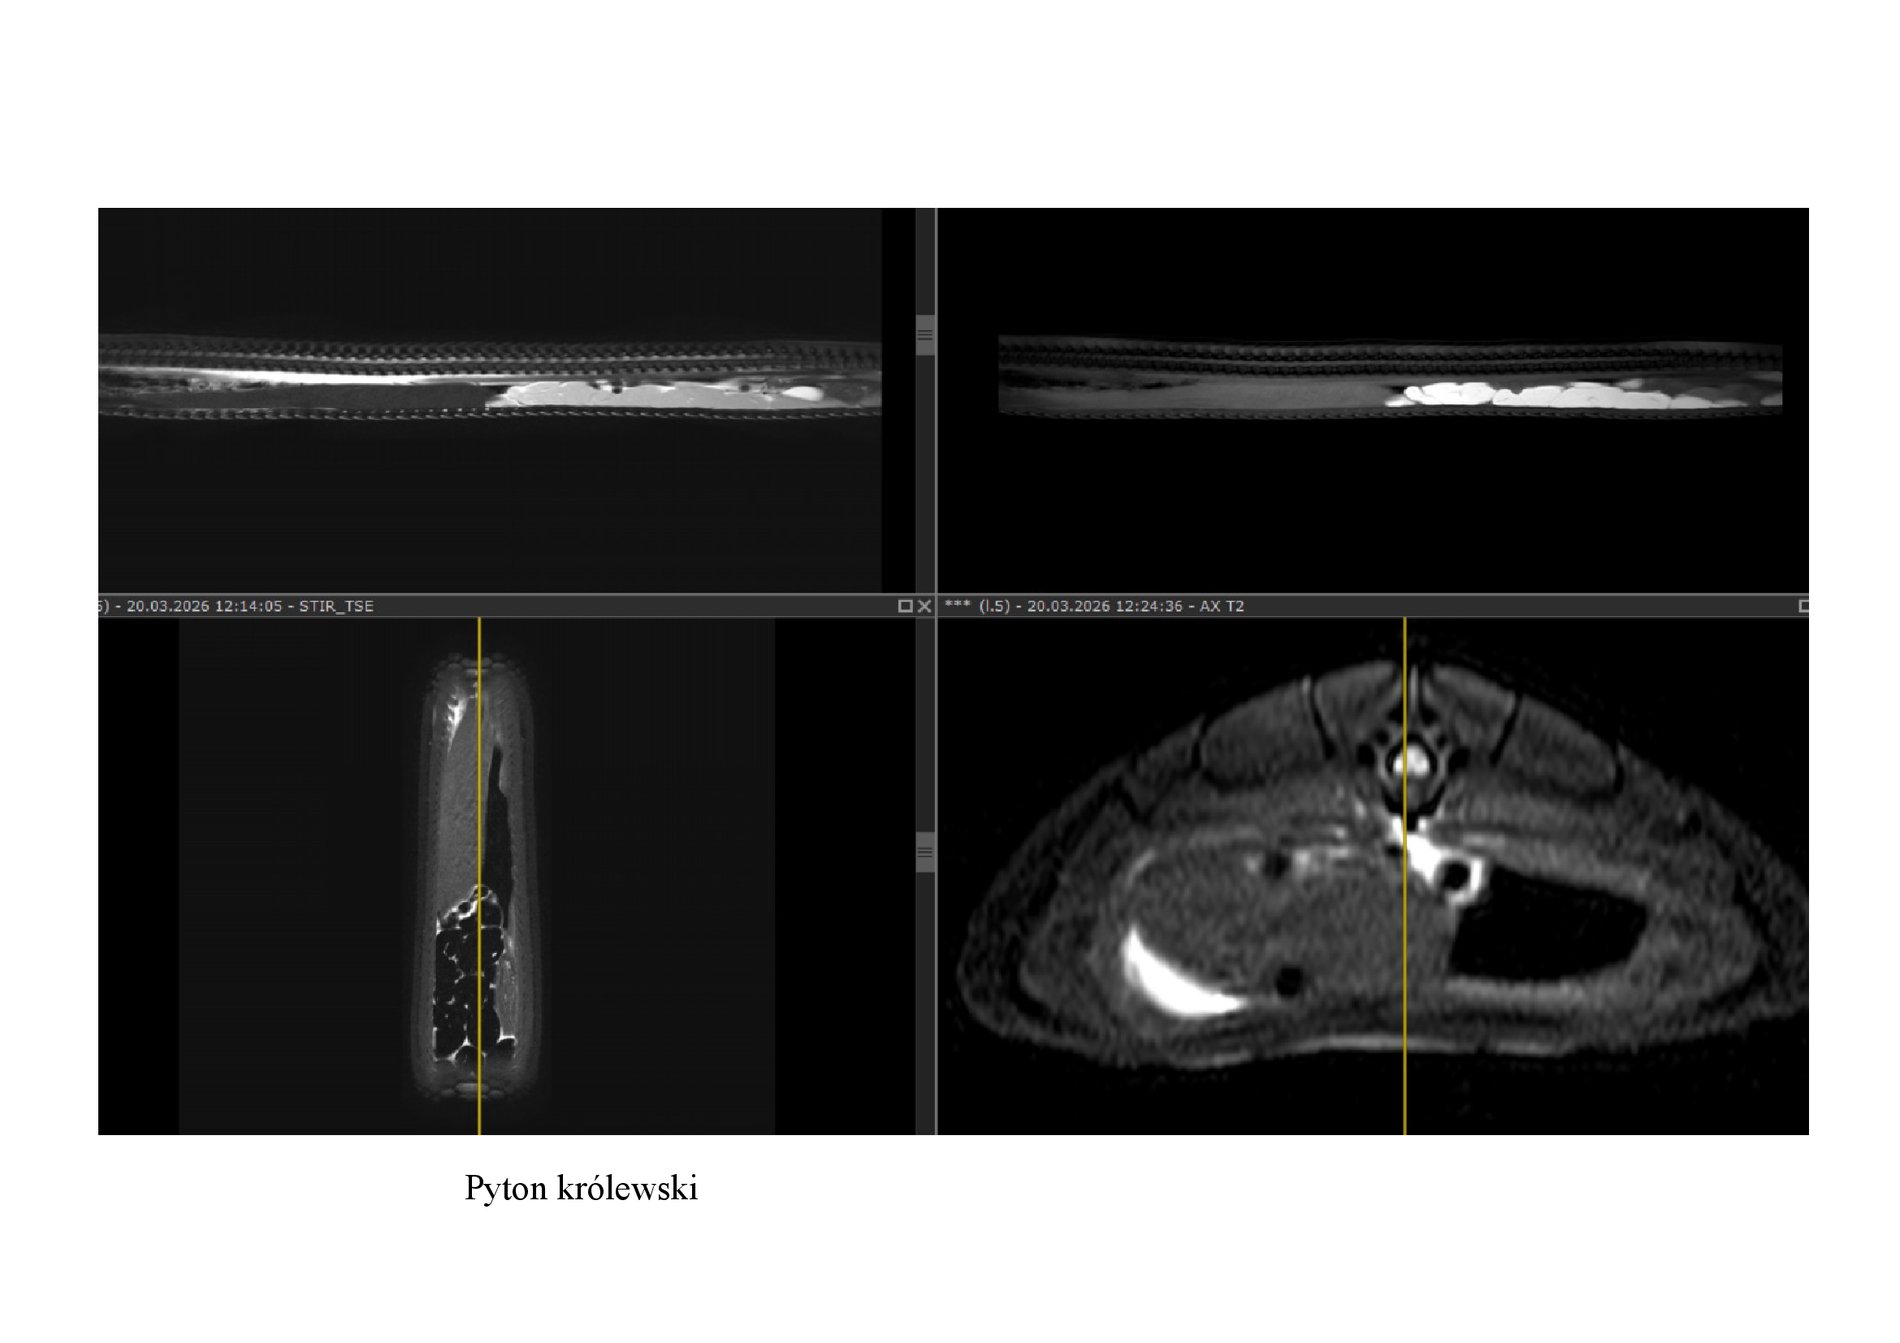

Twój żółw choruje? A może wąż? W Pracowni Rezonansu Magnetycznego Uniwersytetu Przyrodniczego we Wrocławiu badane są nie tylko psy i koty, choć to właśnie one są tu kierowane najczęściej. Pacjentami bywają tu nawet dzikie borsuki oraz lwy, pingwiny i inne zwierzęta z ogrodów zoologicznych.

Pracownia Rezonansu Magnetycznego w Katedrze i Klinice Chirurgii Wydziału Medycyny Weterynaryjnej UPWr specjalizuje się w zaawansowanej diagnostyce obrazowej zwierząt towarzyszących, przede wszystkim psów i kotów. Ale nie tylko, bo coraz częściej pacjentami są tam inne zwierzęta, np żółwie i węże.

Pracownia dysponuje wysokopolowym aparatem Philips Ingenia (1,5T). W ubiegłym roku, po zakupieniu najnowszego oprogramowania, badanie udało się skrócić nawet o 30 procent, co jest szczególnie ważne u starszych zwierząt.